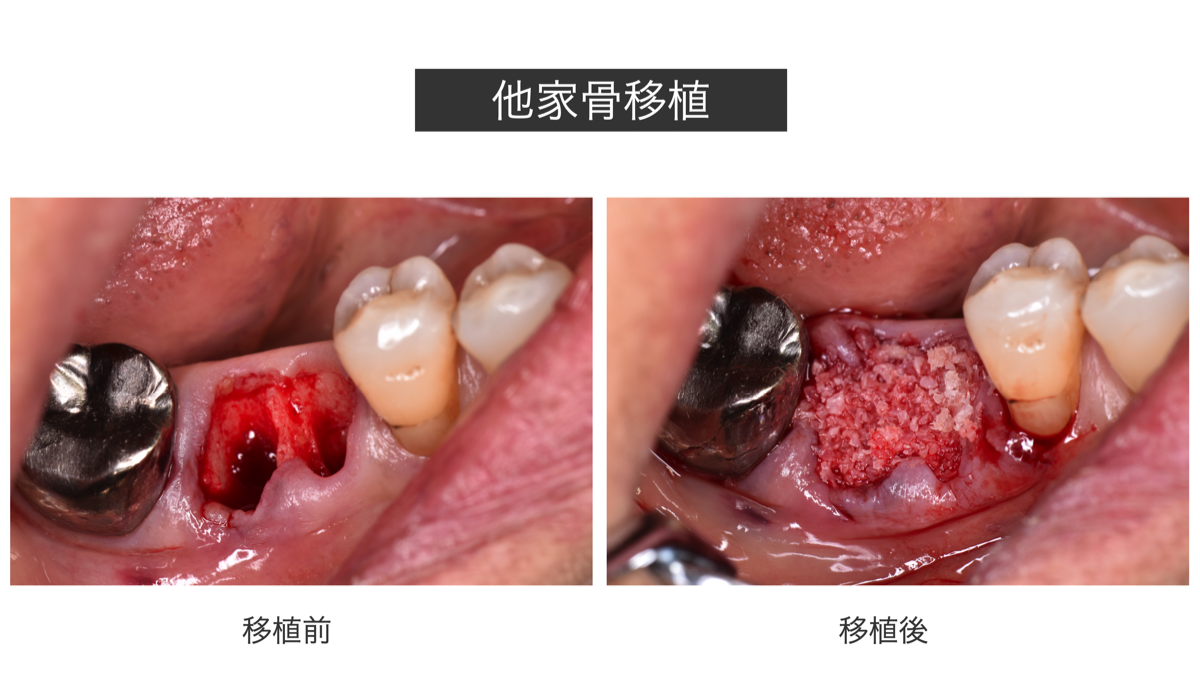

骨をしっかり作る 骨の再生 (GBR)

歯を抜くと廃用により、それまで歯を支えていた骨が急激に萎縮してしまいます。

萎縮した顎骨では、その後のインプラントや固定式ブリッジ、あるいは取り外し式義歯が困難になることもあります。美的な要件を満たさないことすらあります。

後から骨を造成するのは容易い事ではありません。骨の再生や造成は粘膜などの軟組織の処置に比べ、はるかに困難なのでチャンスを逃さない方が賢明と思われます。

そこで歯を抜くと同時に骨を移植し骨量の維持を図ります。

移植する骨は、自分の骨が新鮮で最も良いのですが、供給部位にも手術を要します。

一方、他人の骨の利用は自家新鮮骨より劣りますが、ドナーサイドの手術は不要です。

米国歯科医師会は推奨しています。

上記のPRF単独よりさらにしっかりと歯槽骨を保存する場合に適しています。

萎縮した顎骨では、その後のインプラントや固定式ブリッジ、あるいは取り外し式義歯が困難になることもあります。美的な要件を満たさないことすらあります。

後から骨を造成するのは容易い事ではありません。骨の再生や造成は粘膜などの軟組織の処置に比べ、はるかに困難なのでチャンスを逃さない方が賢明と思われます。

そこで歯を抜くと同時に骨を移植し骨量の維持を図ります。

移植する骨は、自分の骨が新鮮で最も良いのですが、供給部位にも手術を要します。

一方、他人の骨の利用は自家新鮮骨より劣りますが、ドナーサイドの手術は不要です。

米国歯科医師会は推奨しています。

上記のPRF単独よりさらにしっかりと歯槽骨を保存する場合に適しています。